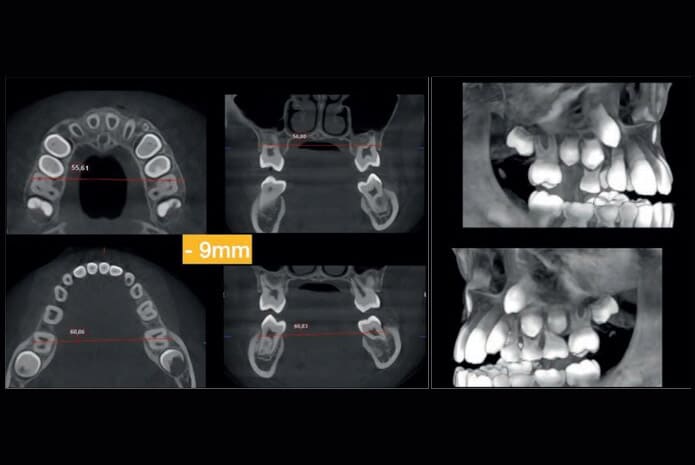

Presentamos un caso clínico de una paciente clase III esqueletal por falta de desarrollo del maxilar superior de 8 años de edad y de género femenino. Sus padres

relatan haber tenido un tratamiento ortopédico ortodóncico anterior sin los resultados deseados. Se solicitan de inmediato registros clínicos fotográficos, imagenológicos, los cuales incluyen radiografía lateral de cráneo y CBCT bimaxilar (Planmeca

ProMax 3D FOV 90 mm x 90 mm).